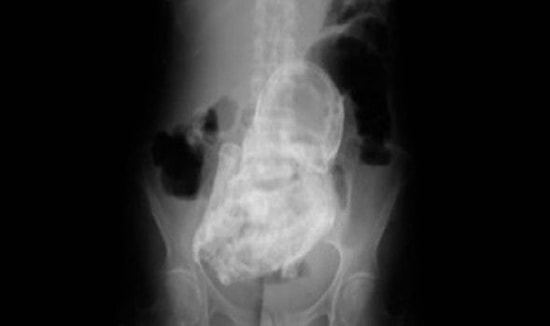

44 Yıldır İçinde Bebek Taşıyor!

Brezilya’da yaşanan kulağa inanılmaz gibi gelen olayda 84 yaşındaki bir kadının tam 44 yıldır içinde bir bebek taşıdığı anlaşıldı. Yaşlı kadın inanılmaz karın ağrıları çekmeye başlayınca hastaneye gitmesiyle tuhaf gerçek açığa çıktı. 84 yaşındaki Brezilyalı kadının içindeki 20 ila 28 haftalık olduğu düşünülen bebek fetusu taşlaşmış vaziyette… İşin daha da ilginç tarafı yaşlı kadın doktorların tüm israrlarına rağmen bebeğin içinden alınmasını reddediyor. X-Ray cihazında yapılan muayene sonucu ortaya çıkan taşlaşmış bebeğin kolları ve ayaklarını bile belirgin şekilde görmek mümkün. Doktorlar adı açıklanmayan yaşlı kadının 44 yıl önce hamile kaldığını söylüyor. Kadın bebeğin hareket etmeyi kesmesi sebebiyle bebeği düşürdüğünü düşünmüş… Aynı zamanda kadının karnında herhangibir genişleme de olmayınca bunca yıl bebek kadının içinde kalmış… Tıp tarihi boyunca çok ender rastlanan bu durumun bir benzeri de 2009 yılında Çin’de yaşanmıştı. 92 yaşındaki bir kadın 60 yıl boyunca bebeği karnında taşımıştı. Literatürde ilk kez bu olay 1582 yılında Fransa’da kaydedildi. O zaman da 68 yaşında ölen Madame Colombe Chatri’ye yapılan otopside kadının 28 yıldır içinde bir bebekle yaşadığı anlaşılmıştı. DIŞ HABERLER/milliyet.com.tr